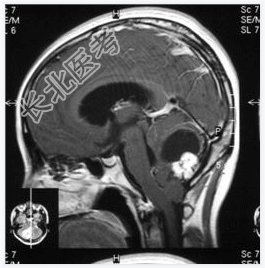

- [材料题] 患者,女性,19岁,因眩晕伴呕吐1周入院。体检:眼震,步态不稳,余未见异常。做头颅MRI检查。

- 简答题1、诊断及依据是什么?

- 简答题2、鉴别诊断有哪些?